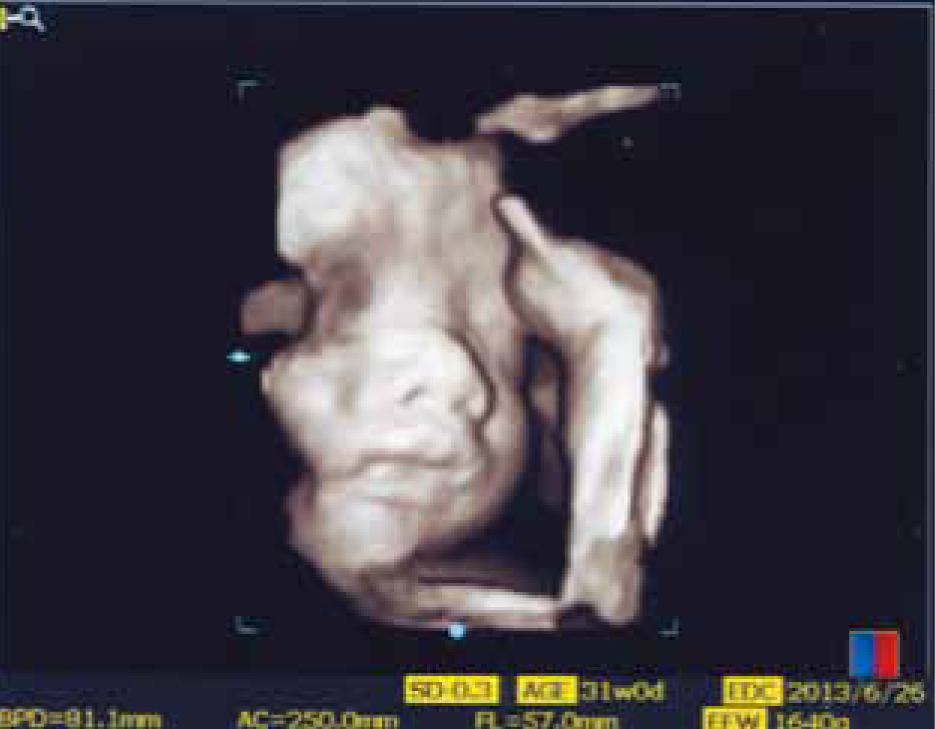

妊婦さんの健診は、妊娠11週末までに3回程度、妊娠12~23週末までは4週毎、24~35週末までは2週毎、それ以降は1週間毎に定期的に行っていきます。その際、超音波検査はほぼ毎回行っています。妊娠初期は、頭蓋骨欠損、無脳症など生命予後不良な形態異常を中心に見ていきます。その他、妊娠10週前後での胎児後頸部の肥厚は、染色体異常との関連が言われています。胎児の臓器は妊娠12週ごろまでにはほぼ完成し、妊娠20週以降胎児形態のスクリーニングが可能となります。胎児超音波スクリーニングとして胎児推定体重の計測、羊水量の異常、胎児形態異常や胎盤位置異常を検査しています。さらに子宮内胎児発育遅延の際の胎児血行動態(パルスドップラー)の計測や毎回ではありませんが、3次元画像である4D超音波による胎児エコー(図1)も行っています。また、先天性心疾患は約1%に見られ、胎児形態異常の中で最も多い疾患です。出生後早期に治療を要する疾患でもあります。通常のスクリーニングで四腔断面、3血管断面、3血管気管断面が基本断面として使用されています。